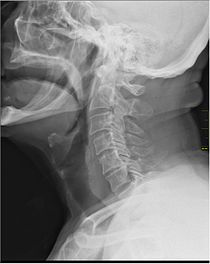

Medical X-Ray imaging EJE04 nevit.jpg

X-ray showing the throat, seen as a dark band to the front of the spine.